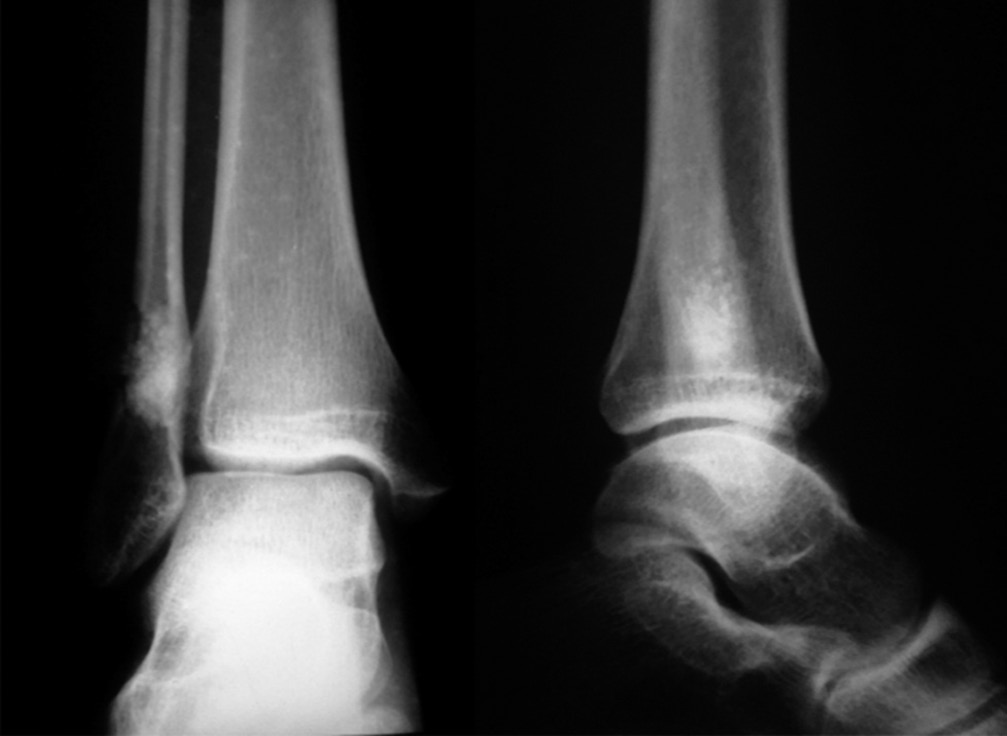

В течение 3 мес. происходила централизация болевого очага в виде усиления болевых ощущений тупого, распирающего характера в области пораженного участка кости (до 6–8 баллов по ВАШ) со значительным усилением в ночное время и при нагрузках. На рентгенограмме наблюдались облитерация костномозговой полости, на магнитно-резонансной томограмме — рубцово-спаечный процесс мягких тканей области нижней трети голени (рис. 3). Отмечались незначительное ограничение амплитуды движений в правом голеностопном суставе, небольшая отечность и температурная асимметрия (местное повышение температуры соответствующего участка кожи).

Рис. 3. Магнитно-резонансная томограмма. Рубцово-спаечный процесс мягких тканей области нижней трети правой голени

28.04.2015 проведено оперативное вмешательство в объеме туннелизации участка нижней трети малоберцовой кости, представленного перестраивающимся костнопластическим материалом. В послеоперационном периоде в течение 2–3 мес. интенсивность боли уменьшилась (до 4–6 баллов по ВАШ), в последующем она достигла прежнего уровня (8 баллов по ВАШ). На компьютерной томограмме спустя 6 мес. после операции отмечались округлый дефект, перерыв кортикального слоя с неравномерными участками склероза костной ткани дистальных отделов малоберцовой кости, отсутствие визуализации костномозговой полости на данном уровне.

При компьютерной томографии на уровне дистального метадиафиза правой малоберцовой кости определялись деформация, остеосклеротические изменения кости на протяжении 29,0 мм с эндостально расположенными участками высокой плотности; кость локально несколько вздута, отмечались сквозные каналы после туннелизации; узурация и кистовидная перестройка задненаружной поверхности правой таранной кости, утолщение прилежащих отделов суставной капсулы правого голеностопного сустава в задненаружных отделах вследствие незначительного отека, количество синовиальной жидкости было несколько увеличено (рис. 4).

Рис. 4. Мультиспиральная компьютерная томография. Деформация, остеосклеротические изменения кости на протяжении 29,0 мм с эндостально расположенными участками высокой плотности; кость локально несколько вздута